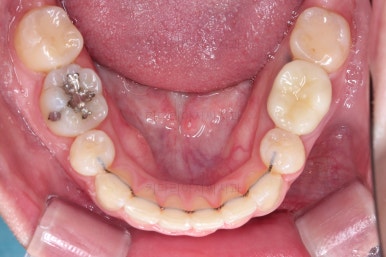

초진 시 입안의 모습입니다.

전반적으로 치열이 삐뚤고, 특정 앞니는 톡 튀어나가 미적으로 좋지 못한 상황이었습니다.

이갈이, 이악물기 습관도 있어서 앞니는 삐뚤어진 채로 치아가 많이 갈려있는 상황이었습니다.